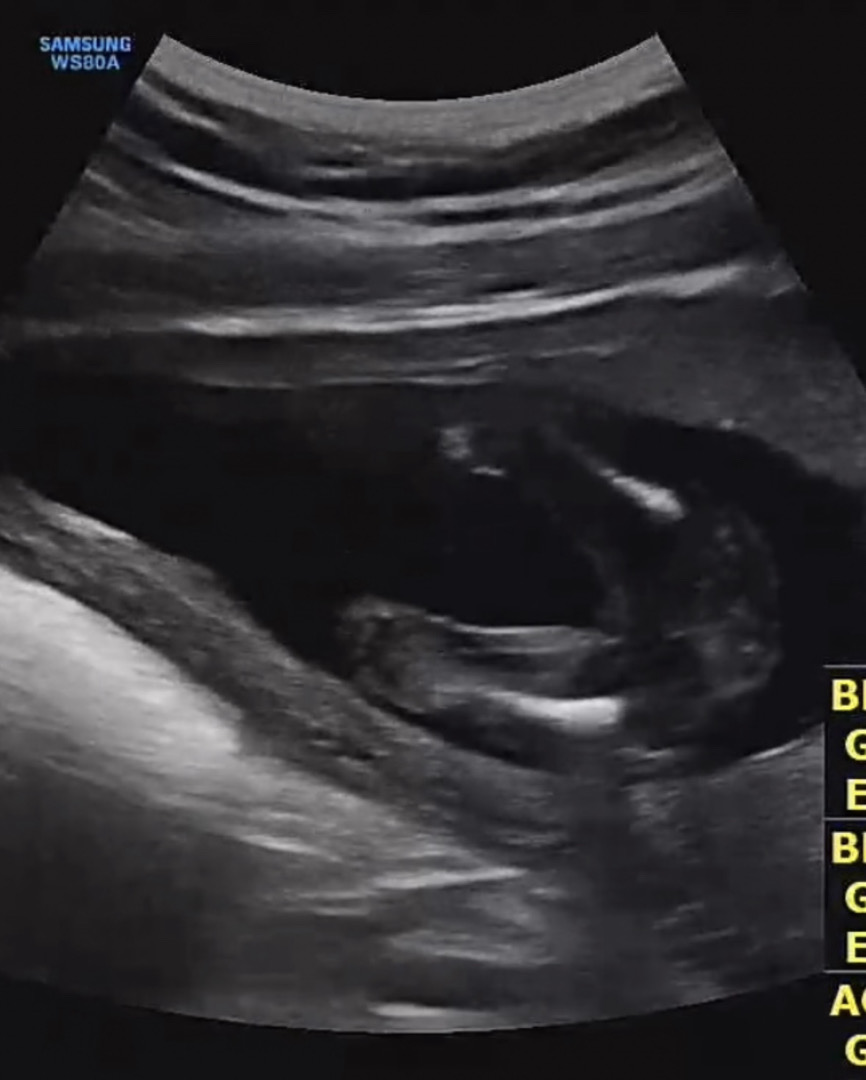

결혼준비하면서 찾아와준 소중한 아기👶🏻 내일 결혼하면서 젠더리빌하려구 미리 풍선도 두가지로 준비했는데 오늘 주말이라 그런지 사람도 많고 ㅜ 아가도 다리를 모으고 있어서 잘 안보이긴하는데 매끈한거보니 여자아이같다고는 하시네요!! 혹시 각도법이나 초음파사진 잘보시는 고수 선배님들 있음 성별 의견 한마디씩 부탁드려용🫶🏻 즐거운 주말 보내세요 ㅎㅎ

결혼 축하드려요~ 자세히 안 보이지만 딸 같아요!